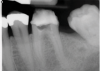

(1.) Preoperative radiograph of teeth Nos. 30 and 31 exhibiting previously treated, symptomatic apical periodontitis and pulp necrosis with a chronic apical abscess and an endodontic-periodontic lesion, respectively.

Figure 1

(2.) Postoperative radiograph after the performance of nonsurgical root canal re-treatment on tooth No. 30 and root canal therapy with hydraulic condensation and bioceramic sealer on both teeth followed by amalgam core buildups. (Case courtesy of David Tran, DMD, Advanced Graduate Program in Endodontics, Harvard School of Dental Medicine).

Figure 2

In endodontics, the techniques and materials are constantly evolving to achieve superior clinical outcomes and improve patient satisfaction. Bioceramic materials, which have historically been used in medicine primarily because of their biocompatibility with human tissue, are ceramic compounds that include alumina, zirconia, bioactive glasses, glass ceramics, hydroxyapatite, calcium silicates, and calcium phosphates.1 These bioactive materials have been favored over other dental materials for a variety of reasons, including their biocompatibility with human hydroxyapatite, enhanced ability to seal, antibacterial and antifungal effects, intrinsic osteoconductive activity, ability to chemically bond to tooth structure, and superior radiopacity (Figure 1 and Figure 2).2